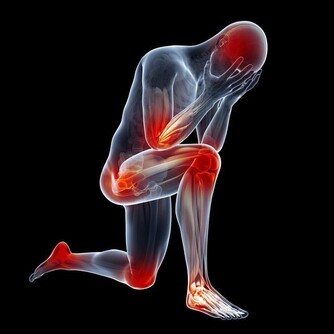

經常久坐,尤其是對我們的腿部健康不利。不管是年輕人還是老年人,你會發現,久坐之後,尤其是我們的下肢感受會比較深,坐久了並不舒服,反而還出現了腿麻、腿腫痛的情況。

這是因為什麼呢?其實道理非常簡單,當我們一直久坐的時候,我們身上有很多的血管,而血液流通也是時時刻刻的。我們一直保持一個姿勢,人在坐著的狀態下,血液流向的地方比較多的就是雙腿了。

沒有了運動的支持,下肢的血液循環變慢,就容易讓血管變得擁堵。在臨床上也發現,靜脈曲張、下肢血栓的人,最好不要久坐、久站,更不要久躺,久躺在這3個方式當中,算是可以讓機體消耗熱量非常低的了,只會讓人越變越懶。

對於年紀輕輕的人,也會因為不良的坐姿,增加頸椎、腰椎的壓力,容易罹患頸椎病、腰椎病,這也是我們大家不能忽視的。